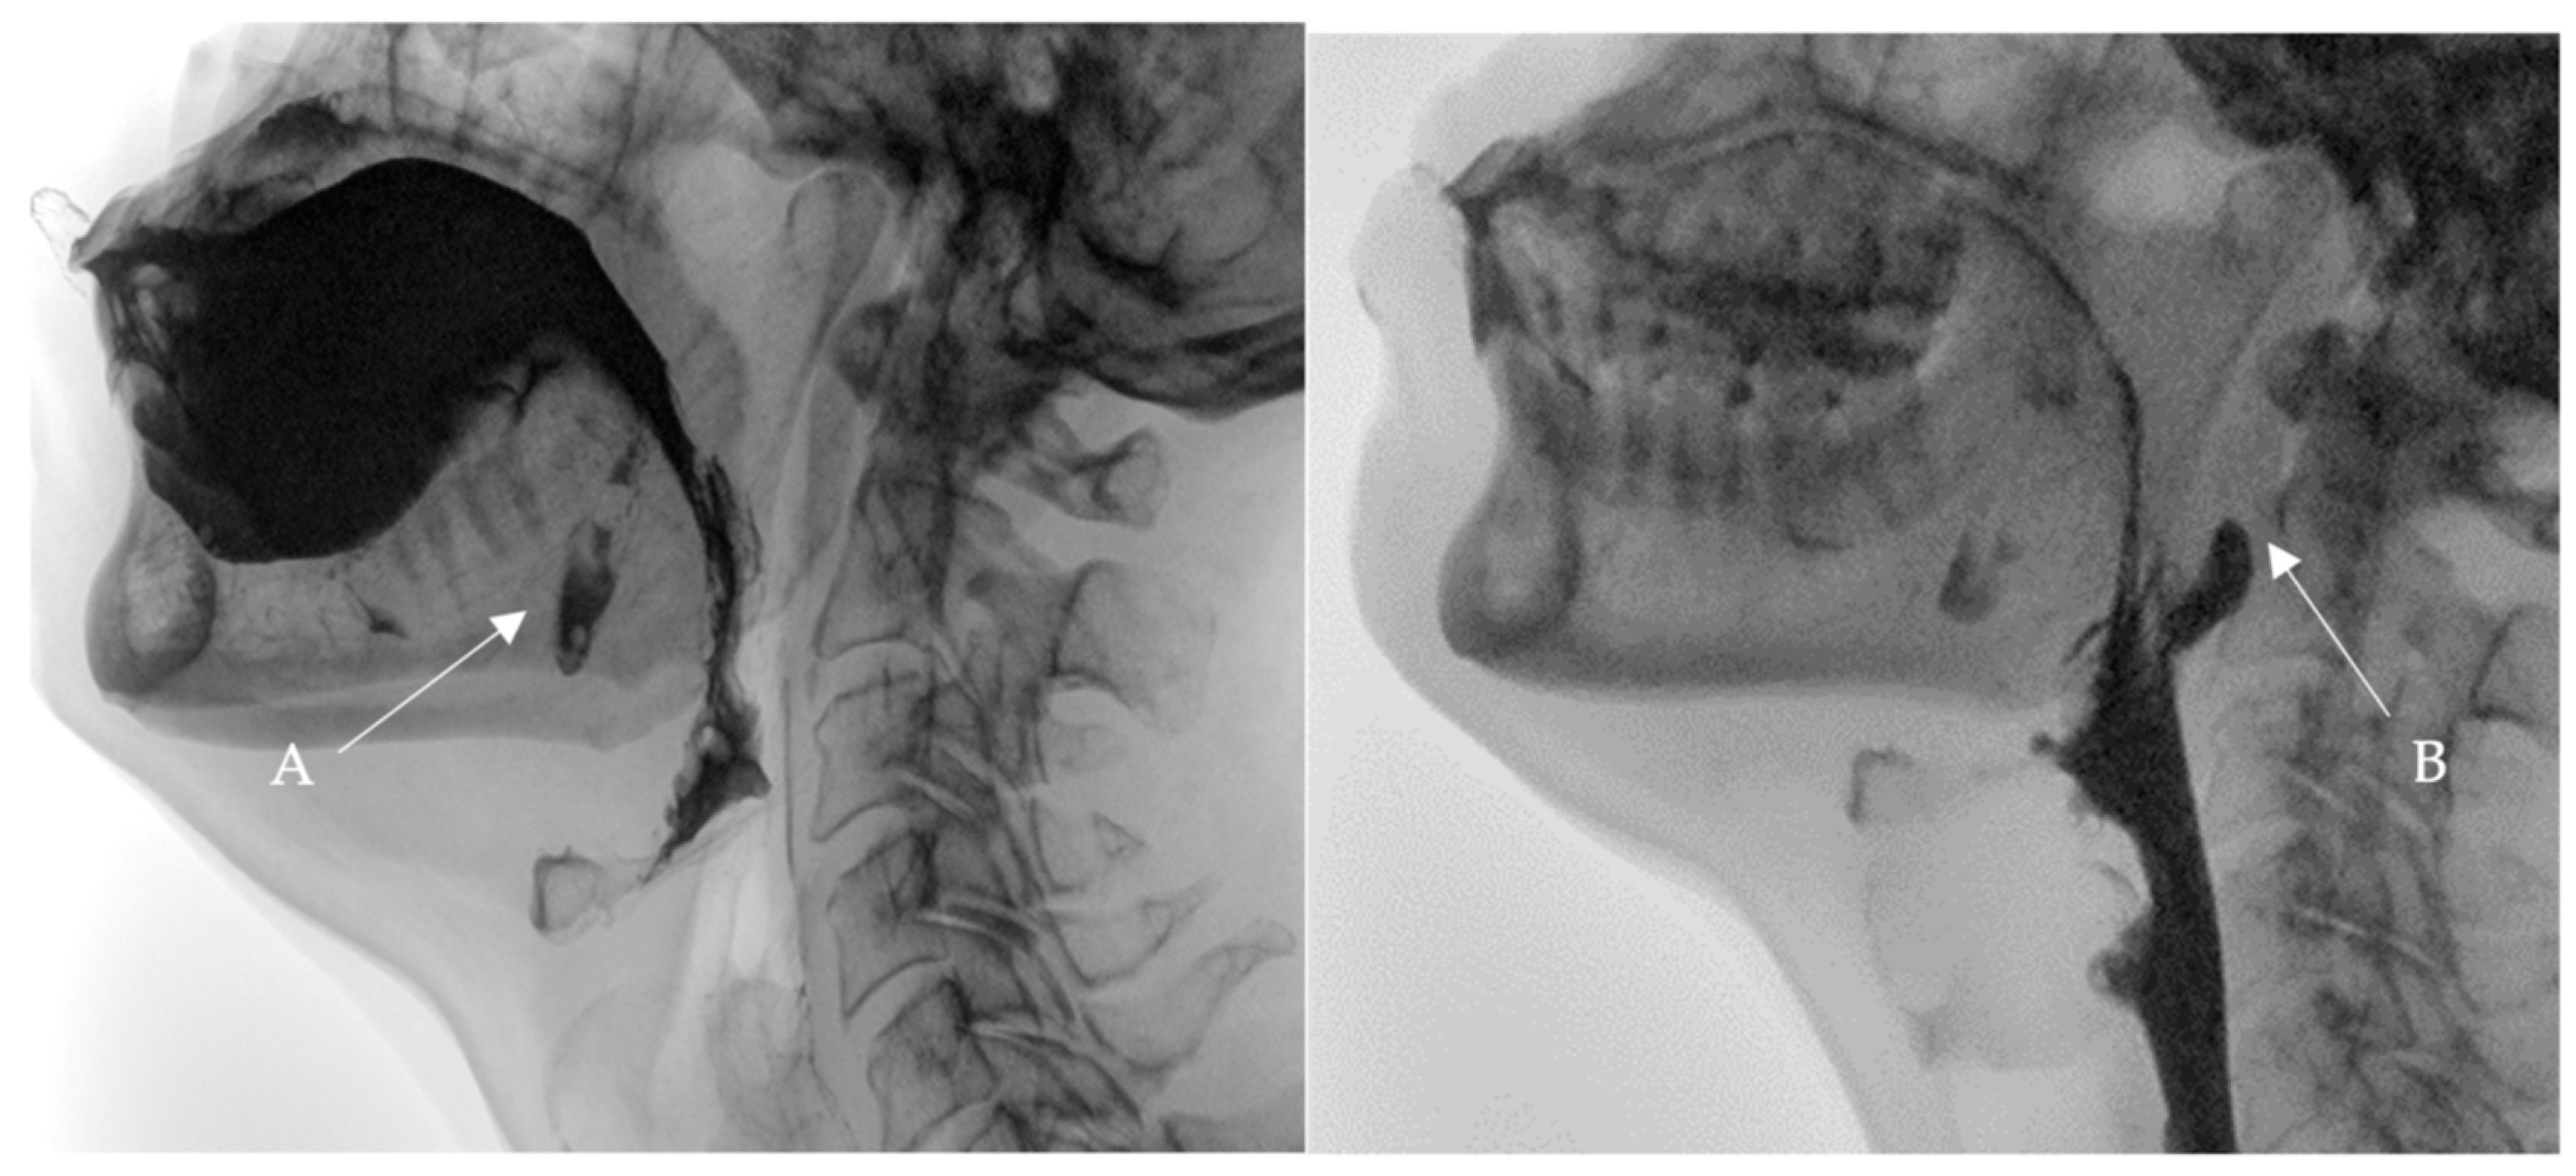

• A videofluoroscopic swallowing study (VFSS) was conducted to assess the oral, pharyngeal, and esophageal stages of swallowing with lateral and anteroposterior views using liquids of thin, thick, and pureed consistencies. The study, conducted by an SLP and a radiologist, showed two posterior inferior oral pouches (buccal diverticula) clearly seen on the floor of the mouth after swallowing. Moreover, two posterior pharyngeal wall pouches (diverticula) in the oropharynx at the level of the second cervical vertebra were visualized (Figure 1 and Figure 2) in addition to regurgitation and flaccid epiglottis. However, no aspiration or penetration was seen during the study.

Figure 1. Selected still images from VFSS, lateral view: bolus pooling and residual contrast in (A). buccal diverticula and (B). pharyngeal diverticulum.

Figure 2. Selected still images from VFSS, lateral view: simultaneous bolus pooling and contrast residue in (A) two buccal and (B) two pharyngeal diverticula.